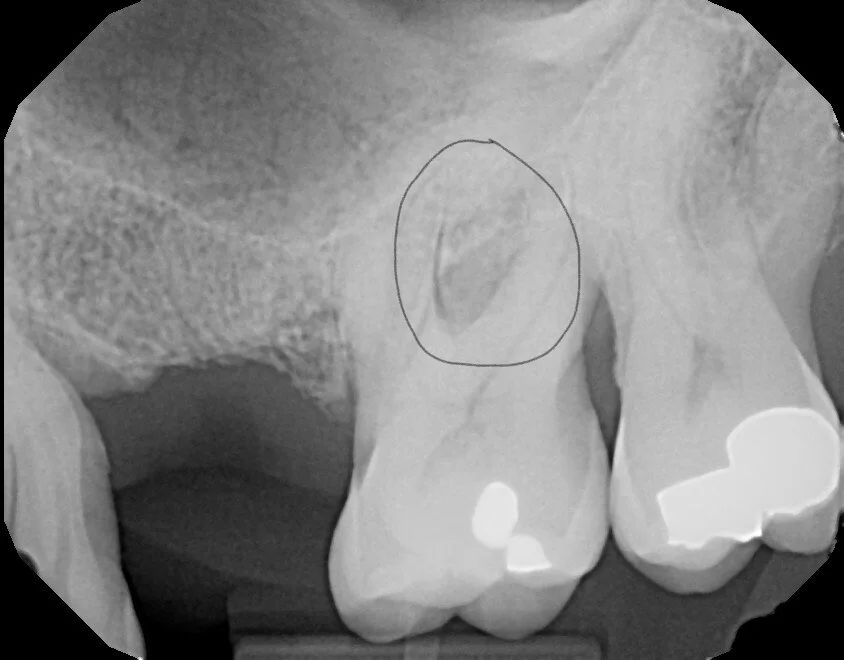

Periodontal abscess Inside CIrcle

Periodontal abscesses involve the gums (gingiva) and bone around the tooth. They are mainly due to excessive plaque and tartar build-up under the gums in the presence of diets that include processed carbohydrates and/or smoking. Antibiotics alone can't cure them. Sometimes it is due to food impaction, in which case removing the food will cure the infection. The pathogenic germs produce toxins that destroy the gums and bone around the tooth, referred to as periodontal disease. Amazingly, this condition causes few overt symptoms, as it is generally a chronic condition. Sometimes it can flare up and become an acute infection where the primary symptoms are pain, swelling, and bleeding. Deep cleanings and surgery are the recommended treatments. As you can see from the x-ray above, they reside deep within the bone, and at-home treatments will not penetrate into the jaw to produce any curative effect.